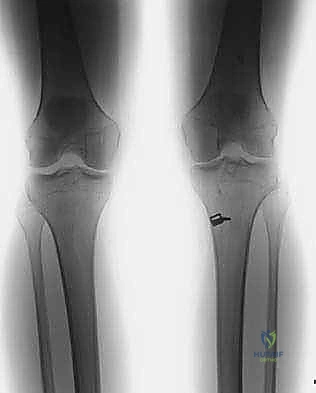

* الأشعة السينية (X-rays): ضرورية لتقييم اتساع الأنفاق العظمية السابقة (Tunnel Widening)، مواقع مسامير التثبيت القديمة، ووجود أي علامات لخشونة المفصل أو انحراف محوري.

* الأشعة المقطعية (CT Scan): في حالات الفشل الجراحي، تعتبر الأشعة المقطعية السلاح الأهم. فهي توفر نمذجة ثلاثية الأبعاد (3D) دقيقة جداً لمواقع الأنفاق العظمية القديمة وحجمها، مما يساعد الدكتور هطيف في اتخاذ قرار حاسم: هل يمكن حفر أنفاق جديدة فوراً، أم يجب إجراء الجراحة على مرحلتين؟

بناءً على الأشعة المقطعية (CT Scan)، يحدد الدكتور هطيف مسار الجراحة: